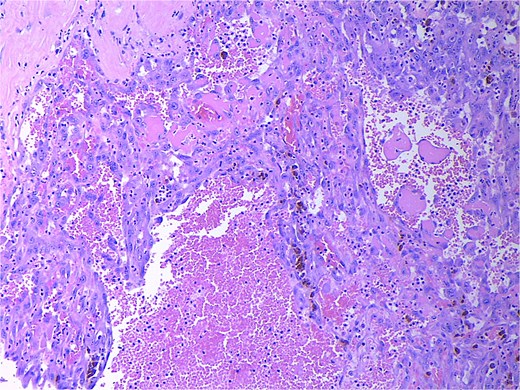

Final pathology revealed an angiosarcoma of the adrenal gland. Sections showed a predominantly hemorrhagic and necrotic mass with residual vascular forming channels within the adrenal gland (Fig. 2). Cells were pleomorphic spindled to epithelioid and atypical (Figs 3 and 4), with a mitotic count of 12/10 high-power fields. Immunohistochemistry showed positivity for ERG (Fig. 5), CD34, and focal pankeratin and negativity for SF-1, SOX10, Cathepsin-K, and chromogranin. There was no lymphatic or vascular invasion identified, and the margins were uninvolved by the tumor. The left kidney was negative for tumor, and the background adrenocortical parenchyma was benign.

Low power magnification (2×) Hematoxylin and eosin (H&E) showing the angiosarcoma within residual non-neoplastic adrenal cortical tissue. Necrosis is also present.